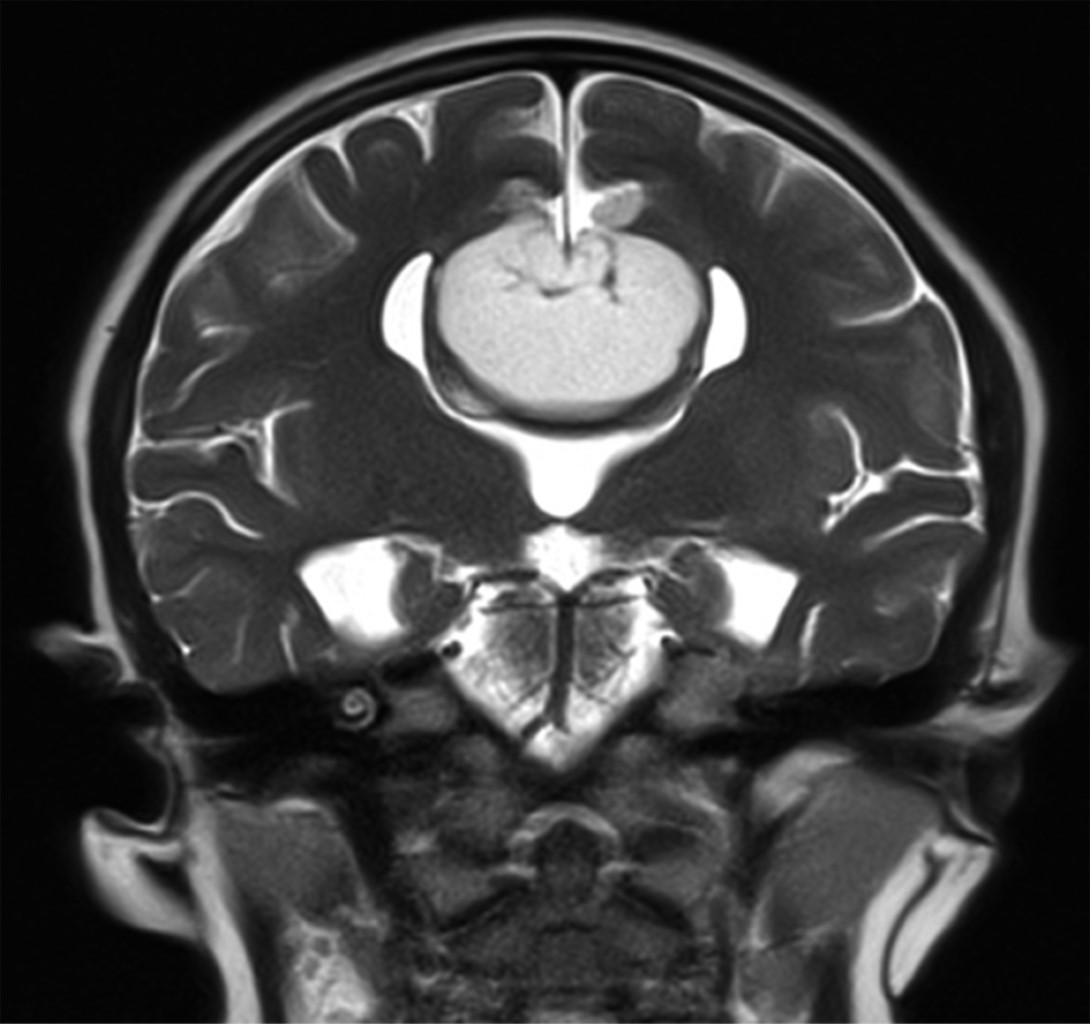

Masculino de siete años edad con antecedente de cefalea, muestra deficiencias en la coordinación motora, equilibrio y lenguaje expresivo. Acude a consulta en medio institucional, donde médico tratante solicita como estudio de abordaje inicial resonancia magnética de encéfalo, en la que se observan cuernos frontales pequeños con dilatación de los trígonos y cuernos occipitales identificando los signos radiológicos en cortes axiales "carro de carreras" (Figura 1) y en cortes coronales "cabeza de alce" (Figura 2). Lo antes descrito se relaciona con disgenesia del cuerpo calloso, la cual se corrobora en cortes sagitales donde no se identifica en la línea media el cuerpo calloso. Además, se identifica masa ubicada en topografía pericallosa de localización anterior, centrada hacia la fisura interhemisférica, lesión de forma irregular de comportamiento hiperintenso en T1 (Figura 1) y T2 (Figura 2), que suprime en secuencia de supresión grasa (Figura 3) y que mide aproximadamente 2.4 × 3.4 × 5.4 cm de diámetro máximo en sus ejes laterolateral, cefalocaudal y rostroventral, respectivamente.

Figura 1